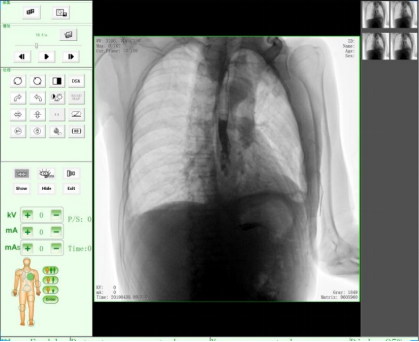

三、實時圖像處理功能

在圖像采集過程中可以對圖像做各種軟件功能鍵的處理,快速呈現醫生閱片所需功能的對應圖像。